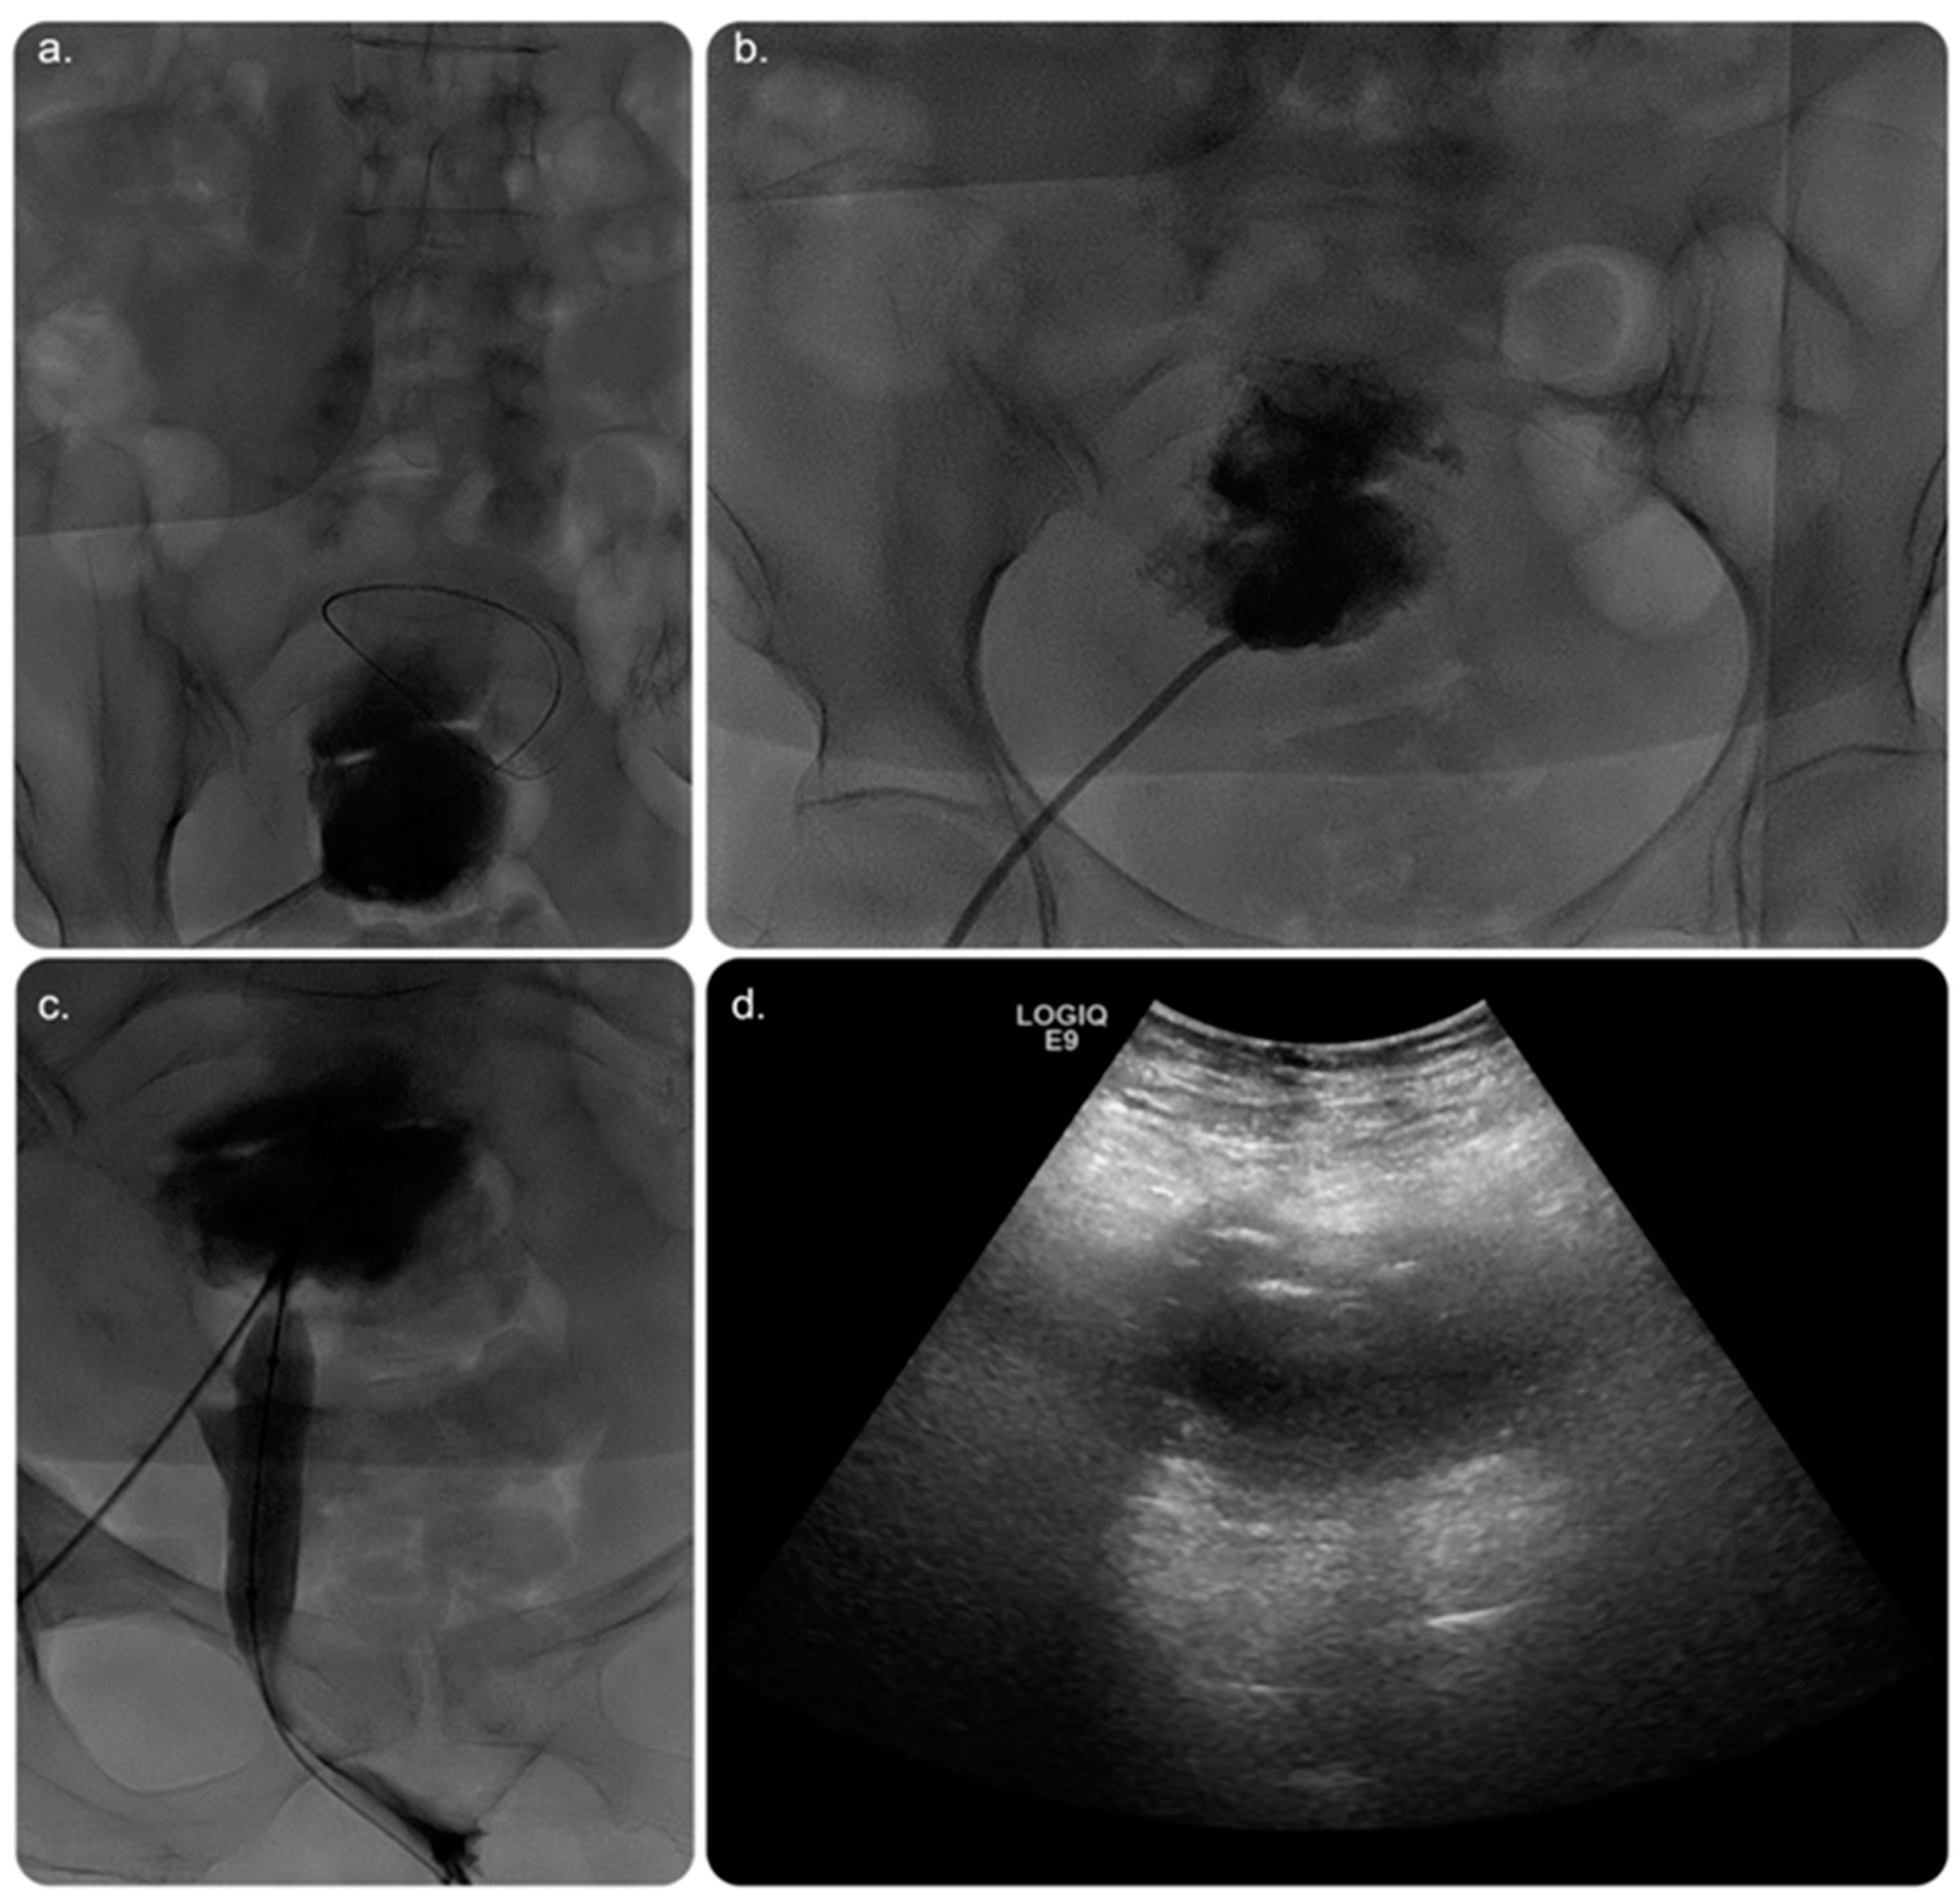

2. Case Presentation